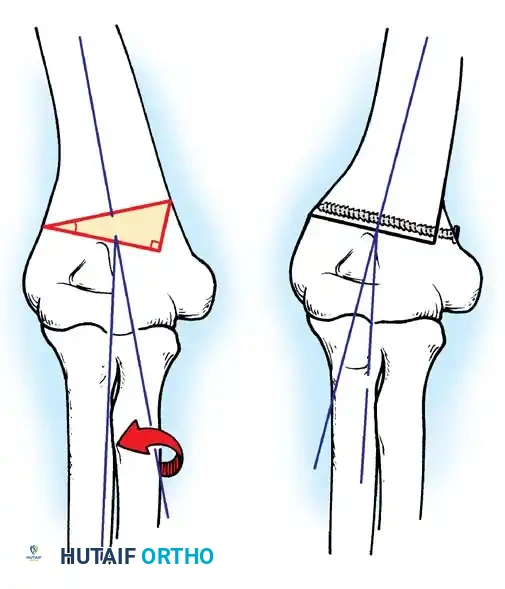

Fig. 33-36 Overcorrection with posterior convexity for anterior dislocation.

Fig. 33-37 Overcorrection with medial convexity for lateral dislocation.